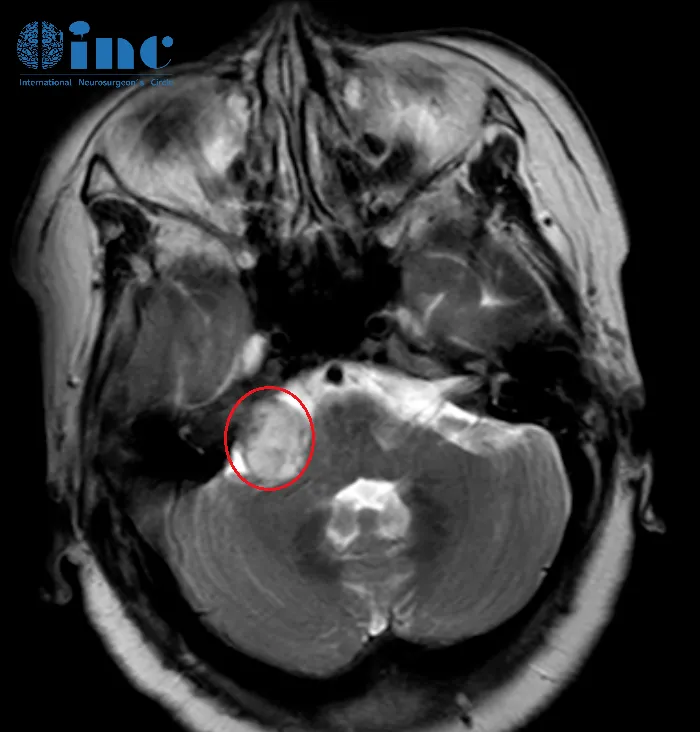

淼淼父母观察到孩子出现一系列异常表现:临床表现为嘴角歪斜、流口水及斜视等症状,这些均为既往未曾出现的体征。经医院系统检查,确诊为颅内巨大海绵状血管瘤,该病灶已引发脑干出血。...